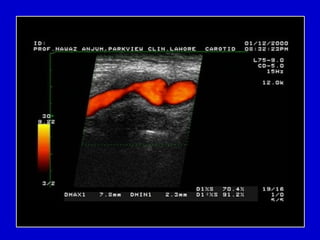

Carotid Artery